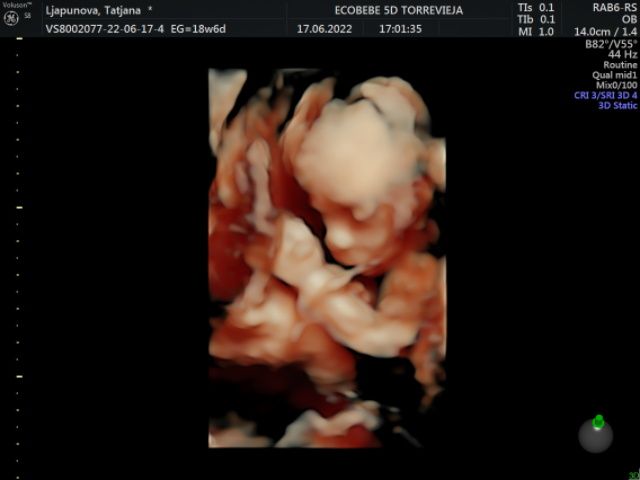

С дочкой делали в 29 недель, была вполне себе похожа на себя. Сейчас последнее делали в 19 недель. Пойдем ещё недель в 28-29. Вот такой он был в 19, уже что то похожее на человека 😅

Вот так было в 21 неделю. Но мне кажется, не похоже на «итоговый результат» :D